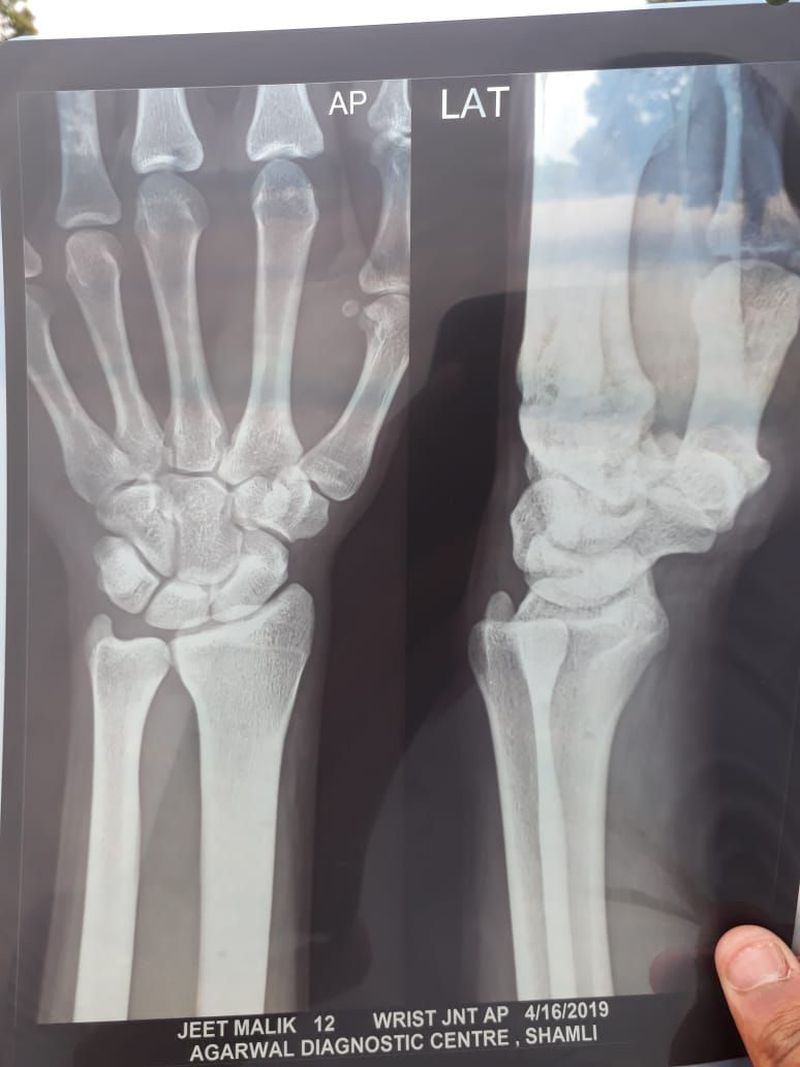

How to Determine age from a left wrist X-ray...????

please elaborate the correct way to know the age of a person only by xray

Growth plates?

You should look at the Hand Bone Age Atlas and compare with similar radiography.